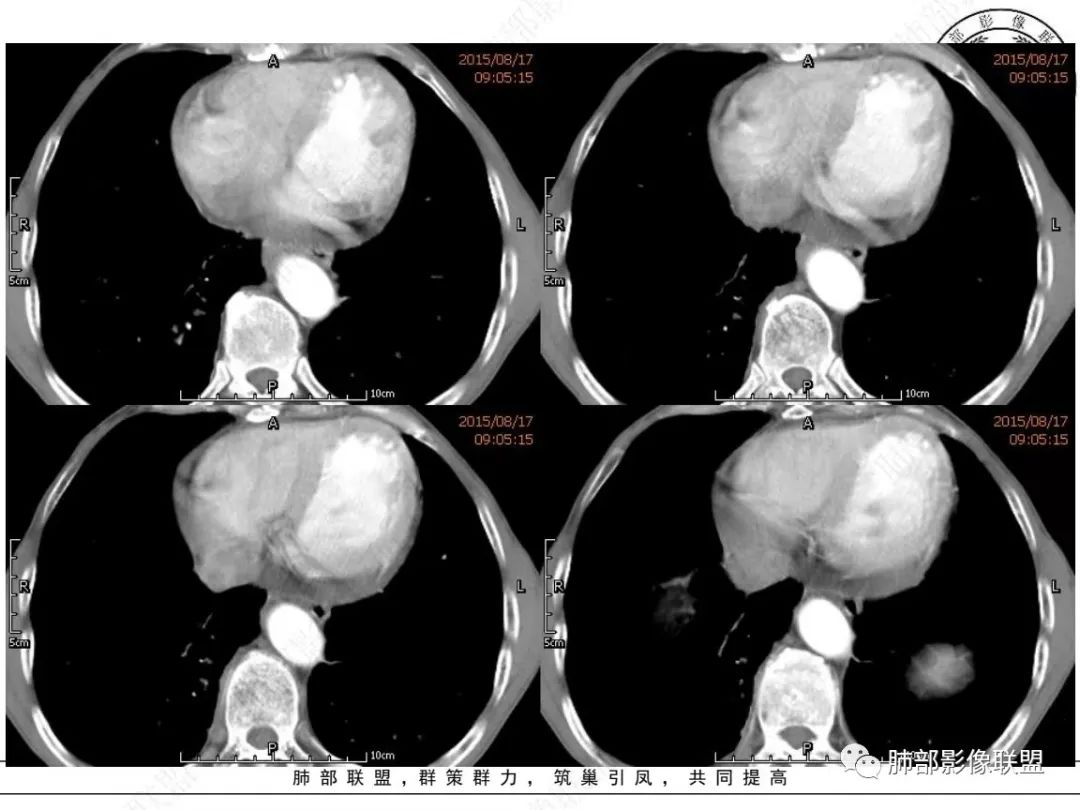

我想CT上,侵袭力强也是特征,破坏力弱表现在血管包绕但形态基本不变,和比较软的感觉。

另外小细胞癌中央区肿块通常没那么圆,有鸭蹼状凸起,周围也不是特别干净,常有小结节或其它阴影

MCL的CT表现为分布无规律的全身多区域淋巴结受侵,少有单一区域淋巴结受累,结外器官受侵多见;MCL有一般NHL淋巴结受累基本CT表现,平扫CT表现为病变密度均匀,受累淋巴结区内呈融合状生长,边界清楚,增强后病灶呈均匀、中等强化,一般病变内无低密度坏死区。确诊需要病理及免疫组化,根据肿瘤组织形态学和免疫组织化学 CD5 及cyclin D1 的表达绝大多数 MCL 可做出明确病理诊。

1.小细胞肺CA:好发吸烟老年男性。常有血液NSE及胃泌素释放肽前体升高。Syn、CgA、CD56阳性。其CT特点可有:冰冻纵隔、冰冻肺门。血管包埋征。针尖样支气管。鸭蹼状凸起。娘小崽大。脂肪间隙消失(常指纵隔及肺门内)。阻塞性炎症不重。侵袭性强。破坏力不强。收缩力弱,内无空泡。沼泽样强化,坏死散而小,坏死不彻底,强化偏低。表面圆钝,角状及条状凸起,蠕虫样表现,腊肠样尾巴(朝肺门侧或背离肺门侧均可以)。胸水多“清澈”(可以理解为淋巴液回流障碍导致的胸水)。点簇状钙化(类似盐与胡椒样)。多见癌性淋巴管炎。另外黄勇老师提出胸膜下的小细胞肺癌具有“山丘征”的特点。